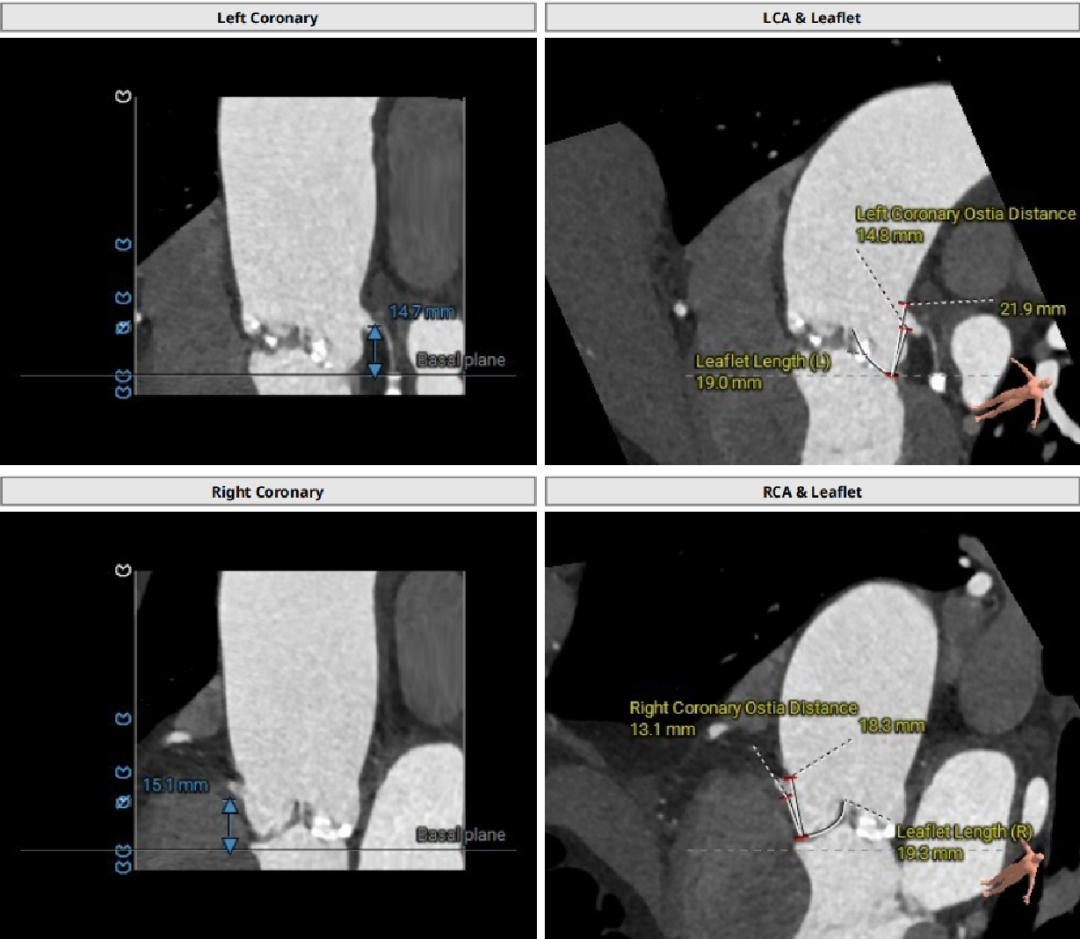

患者CT评估

三叶三窦式主动脉瓣

瓣环周长94.5mm,平均周长径30.1mm;

SOV瓦式窦:32.6mm *35.4mm*36.9mm ;

LVOT周长91.9mm,平均周长径 29.2mm。

STJ平面周长115.2mm;

升主动脉最大直径47.6mm;

瓣叶重度钙化合并增厚,钙化分布不均,主要集中于左冠窦内。

HU953 积分862mm²。

左冠高度14.7mm 右冠高度15.1mm;

瓣口对应瓣叶稍冗长,术中须注意冠脉风险。